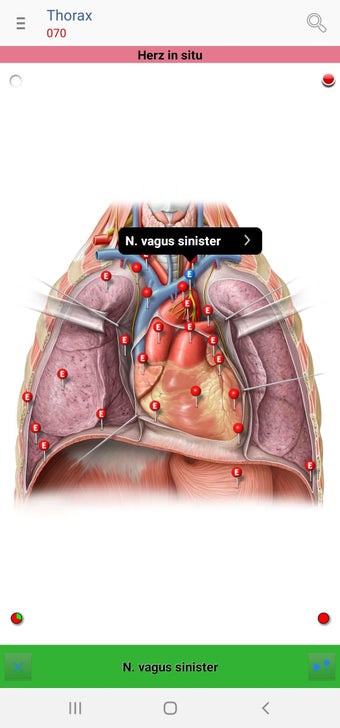

The app consists of different sections, each of which contains information about a specific part of the body. You will learn about the different organs, as well as the muscles, bones, and other important structures. You can test yourself with a unique quiz that consists of multiple-choice questions.